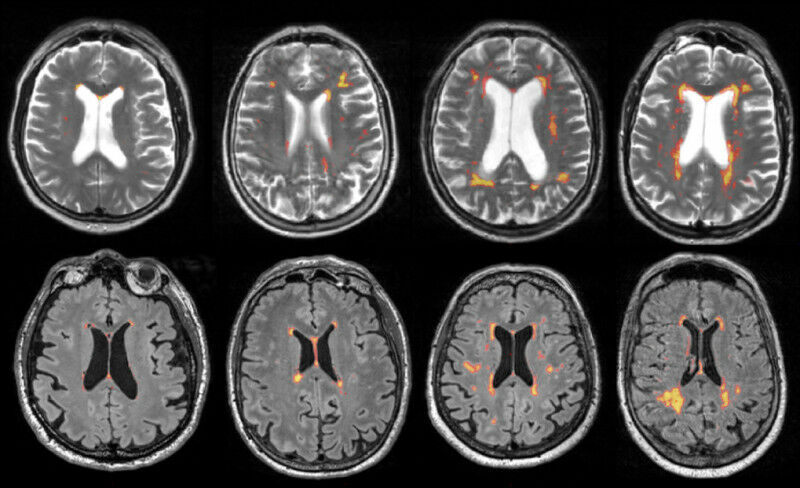

- Tiny brain injuries: Undetected lesions in the brain are a common cause of dementia and can be detected by MRI.

-We have found that lesions occur at typical locations in the brain, presumably because they are based on different mechanisms. In the case of lesions around the ventricles, high blood pressure in particular plays a role, and in the case of lesions in the deep white matter, we suspect a connection with the deposition of amyloid in the vessel walls, a protein that also occurs in Alzheimer's-. As these lesions can become visible from the age of forty, more could be done preventively here, says the researcher.